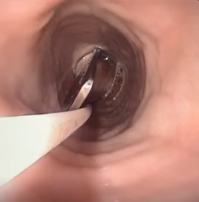

Along with the post, the animal emergency center shared a video showing how the fork was removed from the doggo’s stomach.

Taking out such a large fork using a tube with a handle must have been extremely difficult for the doctor but their precision-made the task seem effortless.